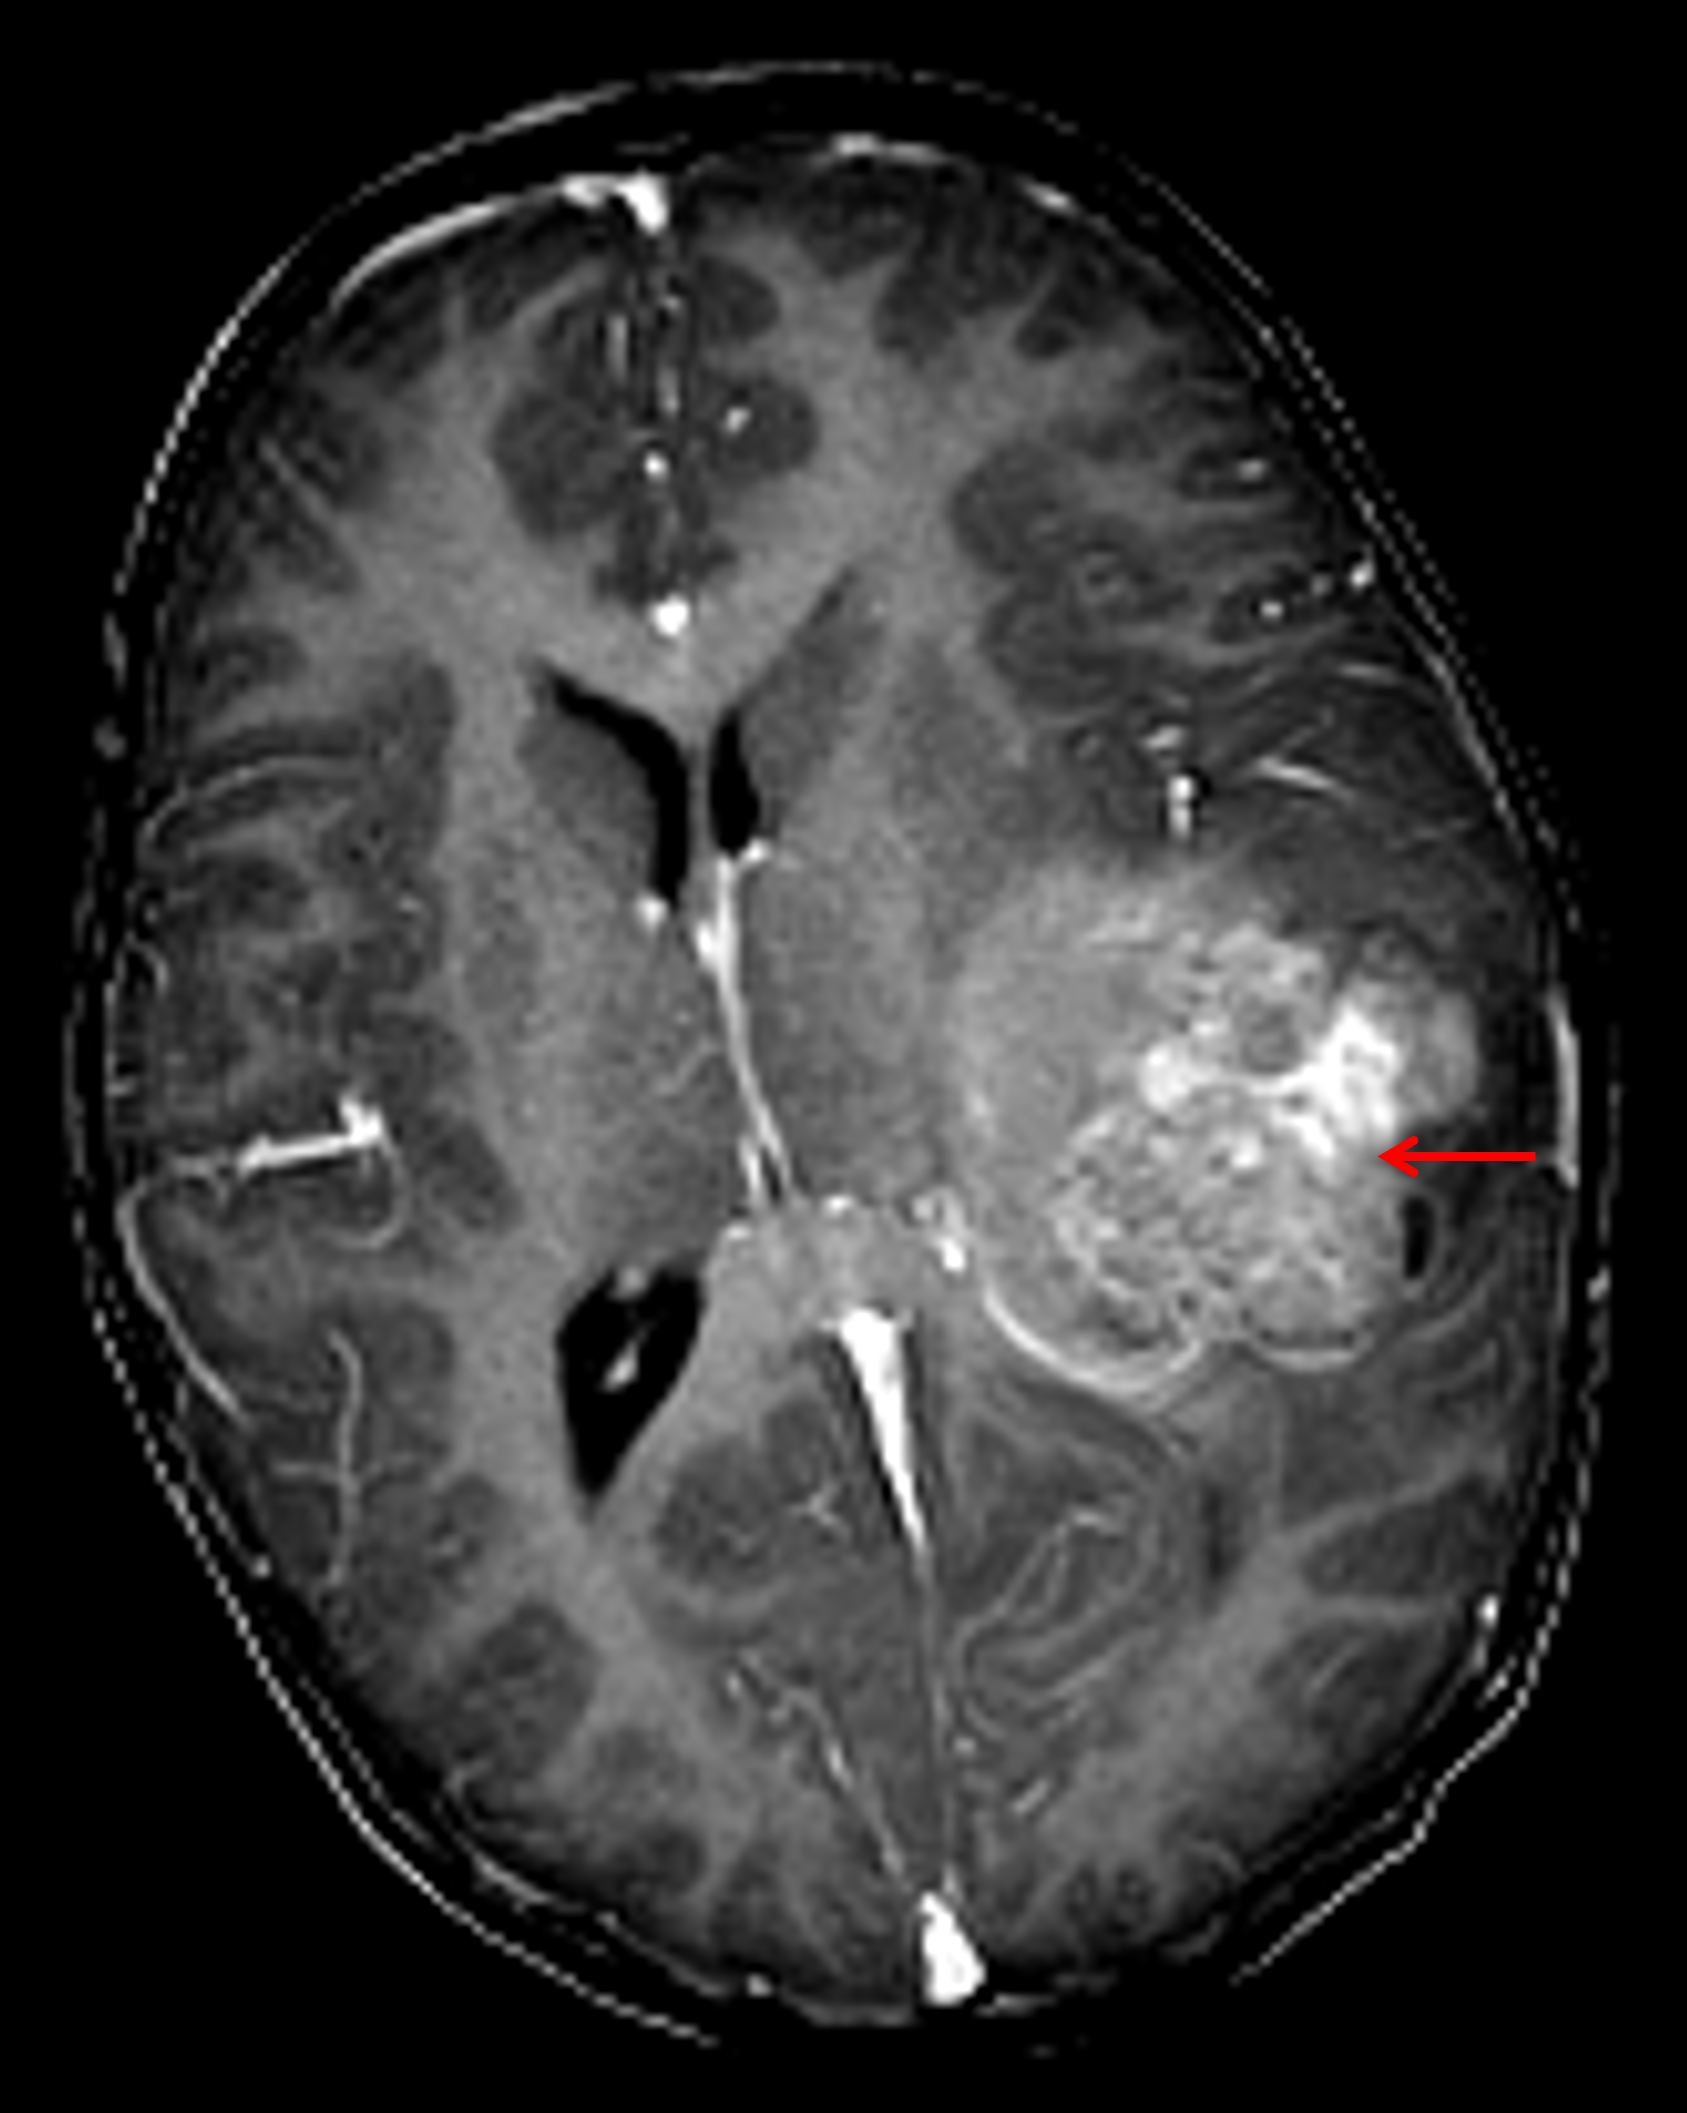

Age: 3

Sex: Male

Indication: Speaking difficulty, imbalance

Atypical teratoid/rhabdoid tumor (AT/RT)